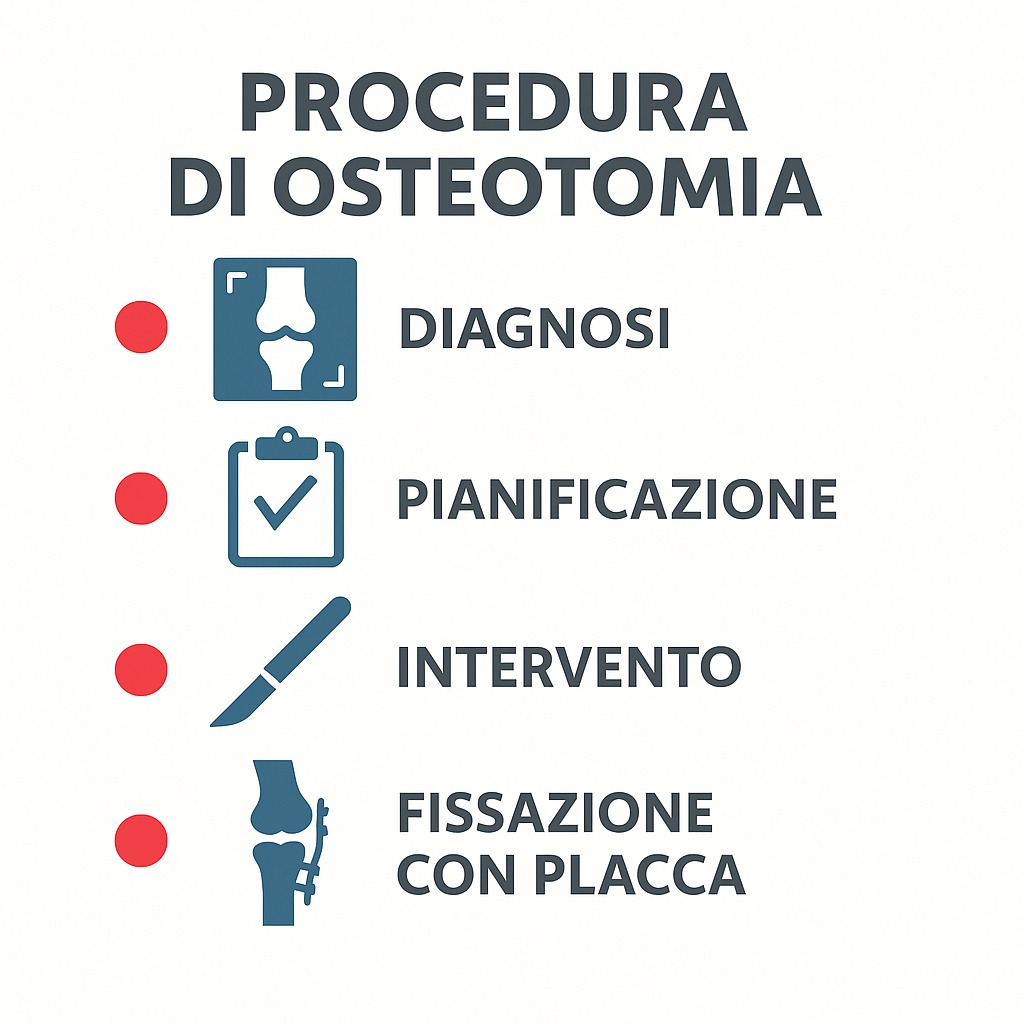

Preparazione pre-operatoria

Il percorso inizia con una valutazione specialistica ortopedica e l’esecuzione di radiografie sotto carico e, se necessario, una risonanza magnetica. Questo permette di misurare la deviazione dell’asse e pianificare con precisione la correzione.

Procedura chirurgica

Il chirurgo esegue un taglio controllato dell’osso tibiale o femorale, effettua la correzione dell’asse e stabilizza il segmento osseo con placche e viti. L’intervento dura in genere 1-2 ore.